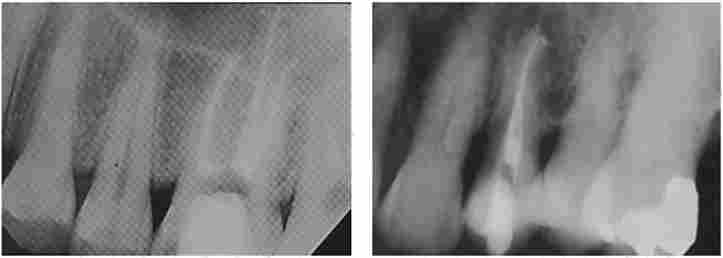

Хворий X., 29 років. Діагноз: «хронічний періодонтит 4.6 (апикальная гранульома), хронічний верхівковий періодонтит 2.6 (апикальная гранульома) і періапікальних абсцес з порожниною 2.4 зубів».

Ендодонтичне лікування виконано з використанням ендодонтичного мікромотора КЗ Etch, наконечника КЗ Headpiece, змінних обертових титано-никеливие інструментів КЗ-файлів і нротейнеров зі змінною конусностью, а також приладу розігріву гутаперчі System В, гутаперчевих штифтів конусности 0,04 і 0,06, плаг- геров, кореневого сіллером АН +.

Пломбування кореневих каналів виконано методом обтурації із застосуванням нагрівають плаггеров і апарату System В. Контролювали проходження каналів апекслокатором (ApexFinder) І але рентгенограммам. Пломбування кореневих каналів підтверджувалося рентгенологічно (рис. 6.5-6.7). Свищ вискоблено. Устя каналів пломбувати низькомодульної матеріалом Filtek Flow із застосуванням адгезивной техніки AdperSingl Bond. Зуби пломбувати композитом Filtek Z250, колір А2. Проведена обробка пломб. Призначено контрольна рентгенографія через 3, 6 і 9-12 місяців. Дано рекомендації пацієнту але гігієну порожнини рота, дієті і контрольним термінів обстеження.

Радіовізіограмма. Пацієнт X., 29 років

Мал. 6.5. Радіовізіограмма. Пацієнт X., 29 років.

Діагноз: К04.5 «Хронічний періодонтит 4.6 зуба»:

канали препаровані інструментами КЗ і запломбовані гуттаперчей до фізіологічного звуження у верхівки коренів

Мал. 6.7. Радіовізіограмма. Пацієнт X., 29 років. Діагноз: К04.6 «периапикальную абсцес з порожниною 2.4 зуба»:

Радіовізіограмма. Пацієнт X., 29 років. діагноз

Мал. 6.6. Радіовізіограмма. Пацієнт X., 29 років. Діагноз: К04.5 «Хронічний періодонтит 2.6 зуба»:

кореневі канали препаровані за допомогою протейперов і запломбовані гуттаперчей КЗ